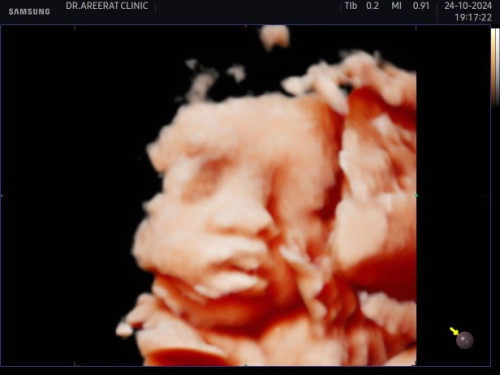

สายสะดือพันคอ 1 รอบ

ตอนนี้ 31W2D เมื่อวานไปซาวน์ 4 มิติ มีสายสะดือพันคอน้อง 1 รอบ หมอบอกให้รอ 34W ค่อยมาดูอีกทีว่า จะพันแน่นขึ้น หรือคลายตัวออก ให้สังเกตการดิ้นของลูก มีใครเจอแบบนี้บ้างมั้ยคะ ทำอะไรได้บ้าง #ขอคำแนะนำกับแม่ๆด้วยนะคะ